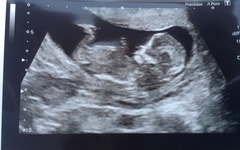

Met with the midwife for the first time and she found a heartbeat, so guessed I was around the 12 week mark, however when I went to the scan was only 10 weeks, the second scan I had in EPU after having gone to A&E with severe abdominal pain for about 3 days?, which turned out to be nothing serious - guess I just panicked because I don't really know what to expect as normal throughout a pregnancy, worried me slightly, and the third is my dating scan.

Next scan booked for the 15th June, however we're tempted to go private and get an early sex scan!! X